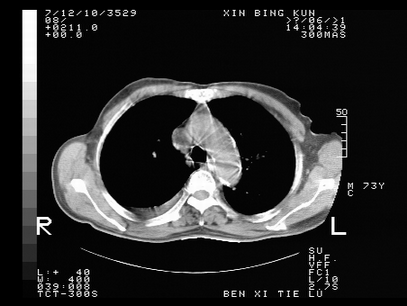

标题: CT10820:男,73岁,病史肺TB,现病史肺炎,直肠CA术后 [打印本页]

双肺间质改变,依据病史双肺多发结节灶考虑转移,少量胸水.

1.两肺结核.2.两肺多发转移瘤.3右侧少量胸腔积液4.主动脉钙化.

双肺多发结节及条片状致密影,右侧少量胸腔积液。临床:直肠ca术后,肺tb病史。综合考虑:1 双肺转移!2 继发性肺结核合并感染!

此人病史较复杂,原有肺结核,直肠癌术后。肺部病灶形态亦呈多形性。因此,不可仅以一种病来解释肺部的病变。双肺多发的类圆形结节灶,结合病史还是首先考虑转移瘤,而双肺其余病灶还需结合化验室检查,结核或肺部感染在无其它检查资料的情况下不好排除。还是那句话----放射科医生不是开照像馆的,我们也是医生,看片一定要多结合临床及其它检查资料。要当一名合格的放射科医生,并不比当一名临床医生容易,我们可别把自已不当医生看。

两肺多发结节影,并见滋养动脉与其相连,考虑 两肺转移. 右侧胸腔积液考虑胸膜转移.

左肺上叶下叶背段,右肺中下叶见多发斑片状、条索状高密度影,兵变周围小结节影形成“树芽”样改变。 左肺上叶舌段近前胸壁处及右肺中叶内侧段见结节影。右侧胸膜腔内见液体密度区。纵隔内未见明确增大淋巴结。考虑左肺上叶舌段近前胸壁处及右肺中叶转移瘤可能性大。两肺继发型肺结核。右侧胸腔积液。